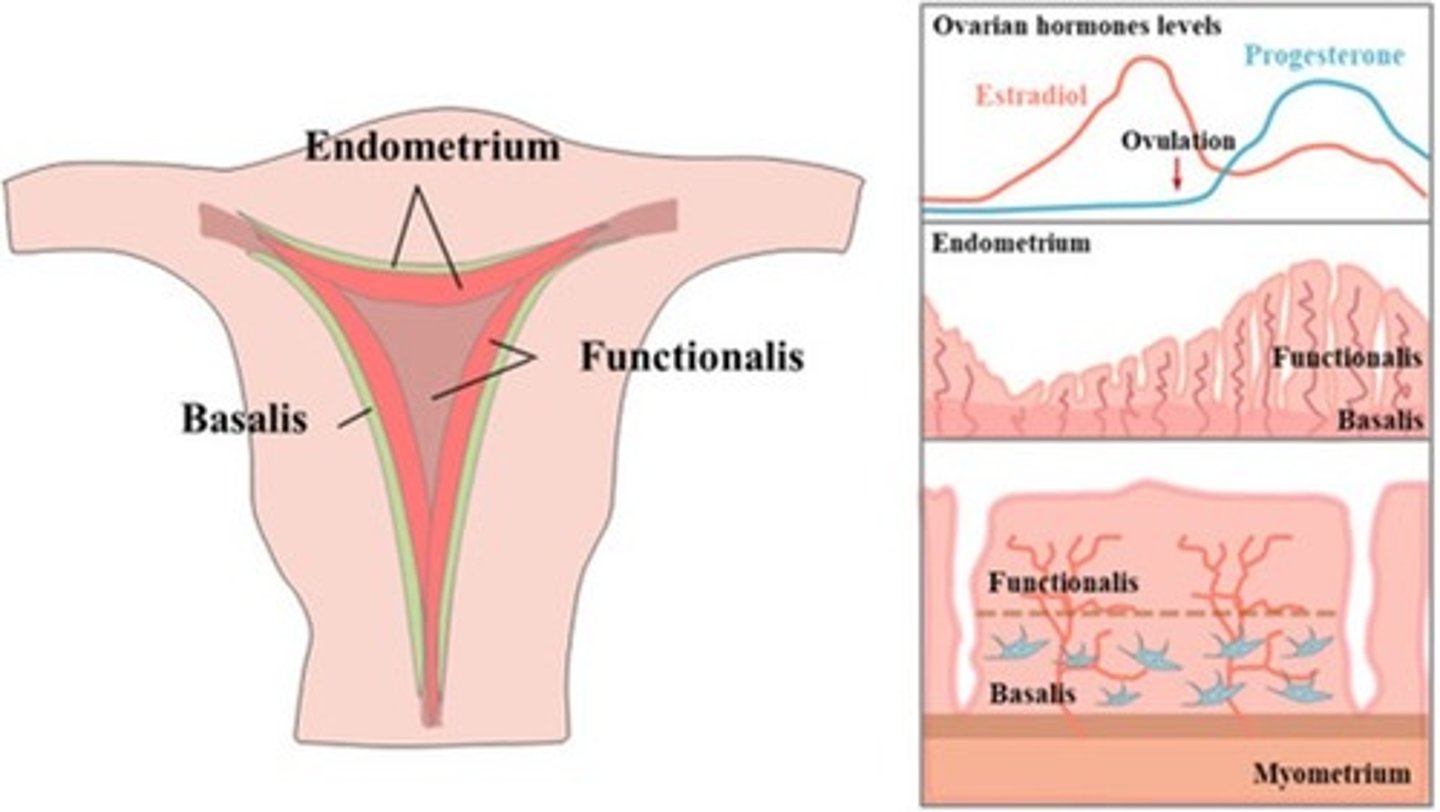

What are the 2 layers of the endometrium?

1. functionalis

2. basalis

The functionalis layer is a ___ layer that ___

superficial; sheds during menstrual cycle

The basalis layer is a ___ layer that is ___

deep; permanent

Menstrual cycle phases:

Days 1-5

Days 6-13

Day 14

Days 15-28

menstrual phase

proliferative phase (preovulatory)

ovulation

secretory phase (postovulatory)

Days 6-13 of the menstrual cycle

- endometrium thickens to prepare for implantation

- estrogen rises

- FSH rises

During the menstrual phase, the endometrium appears ___ and ___

thin; bright

During the early proliferative phase, the endometrium appears ___ and measures ___

bright; 4-8 mm

During the late proliferative phase, the ___ is visible and endometrium thickens to ___

3 line sign; 6-10 mm

During the secretory phase, the endometrium appears ___ and ___ and measures ___

thick; echogenic; 7-14 mm

Days 15-28 of the menstrual cycle

- endometrium is at its thickest

- ruptured dominant follicle (Graafian) becomes corpus luteum

- estrogen and progesterone decrease